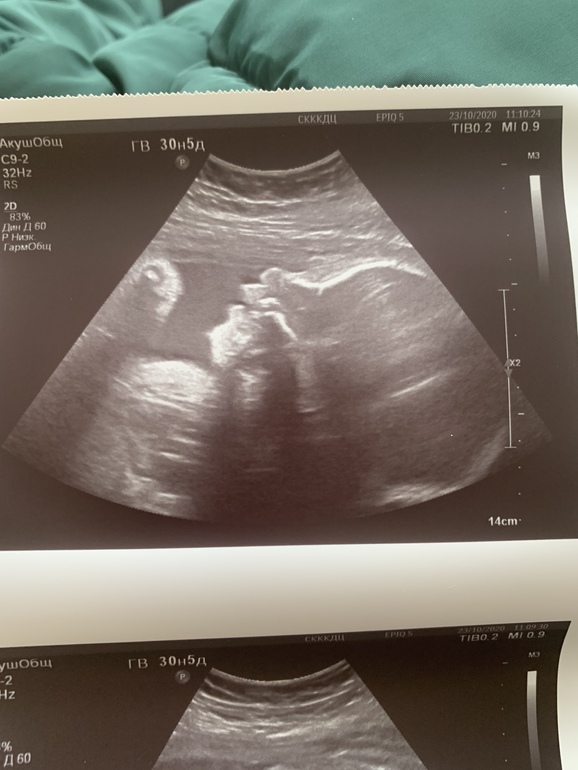

По традиции, третий скрининг😊

Была сегодня на узи, видела малявку, зевала там что-то)

По весу мы уже 1,8кг, я думала поменьше будет. Ручки ножки длинные уже, видимо вся в папу пойдет🥰

Узист сказала, что все у нас хорошо, что развиваемся точно в срок.

Была очень удивлена, что шейка 39мм, степень зрелости плаценты вообще 0-1.

Головкой вниз мы лежим уже давно, ребра мои чувствуют ее пятки😬